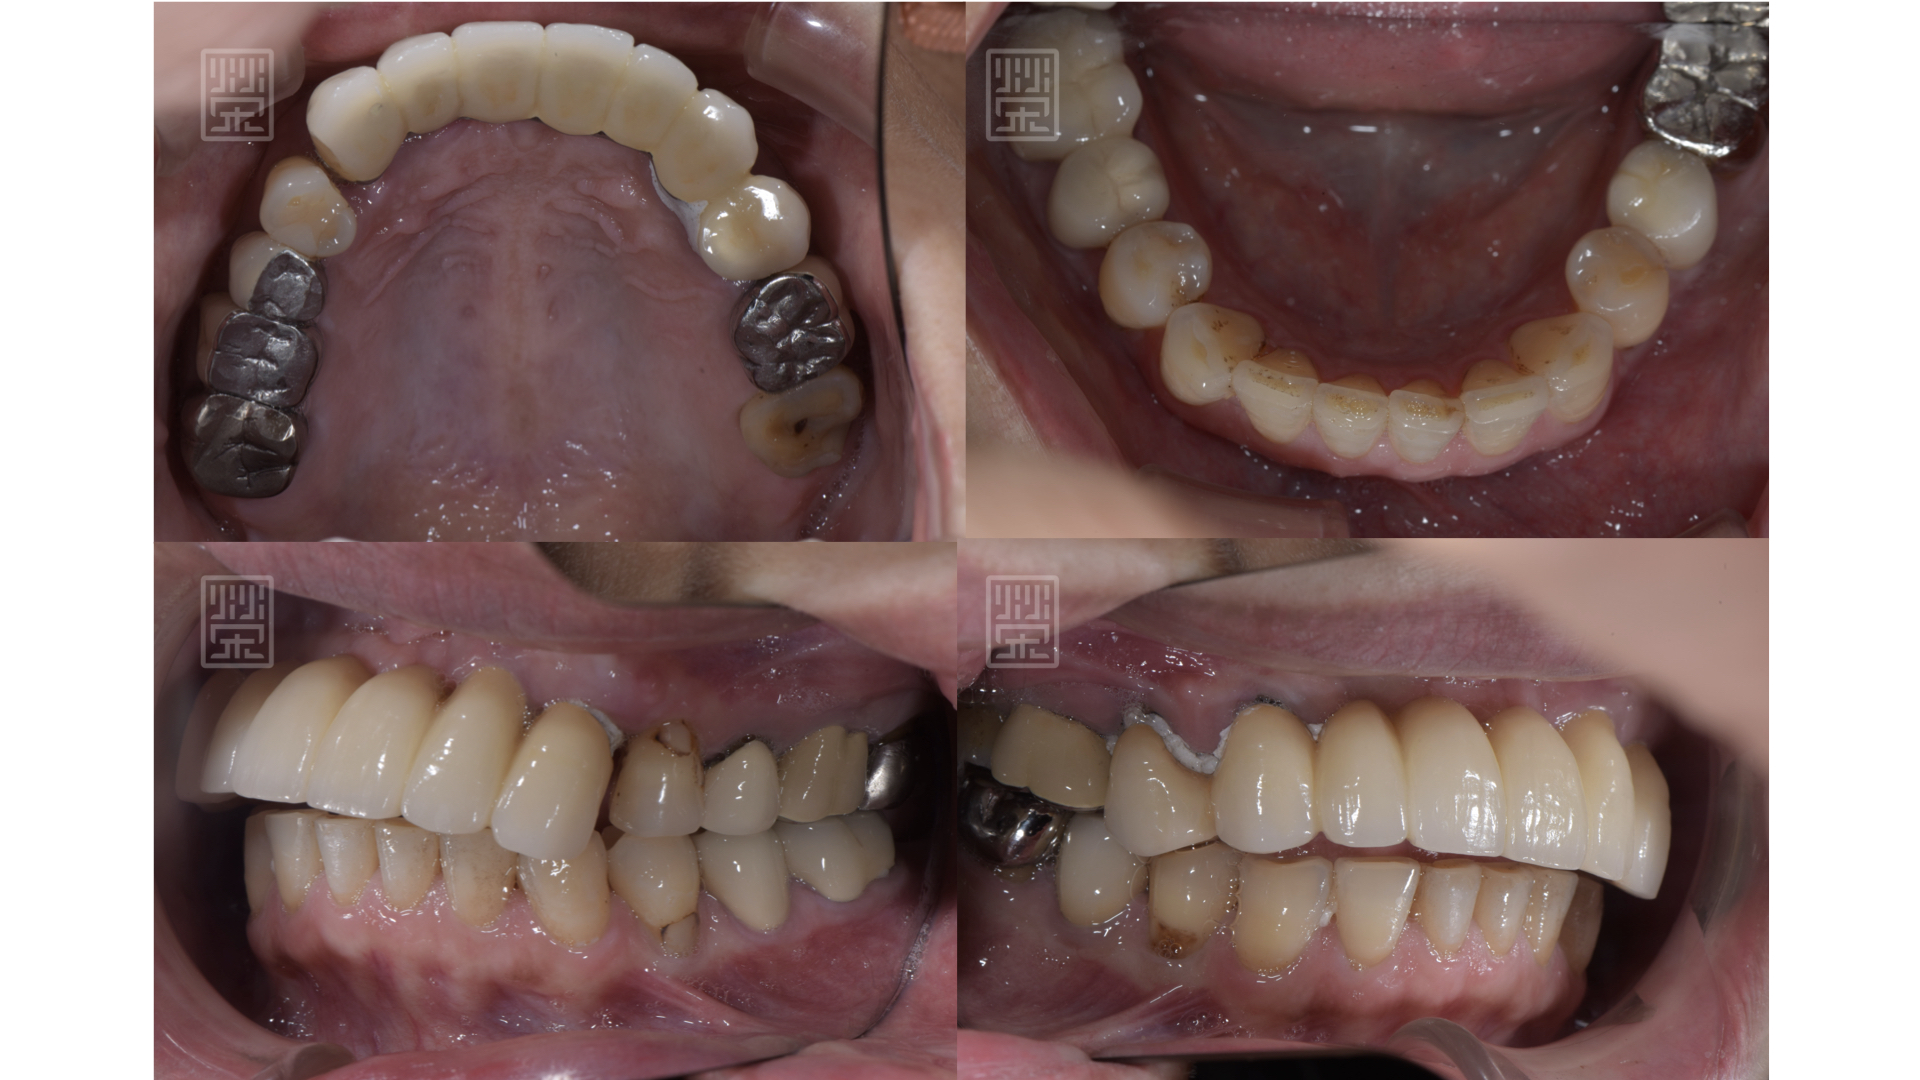

口內照片顯示,假牙黏膠未脫落、邊緣不秘貼,無法正常咀嚼及說話

更換臨時假牙後,恢復外觀與功能